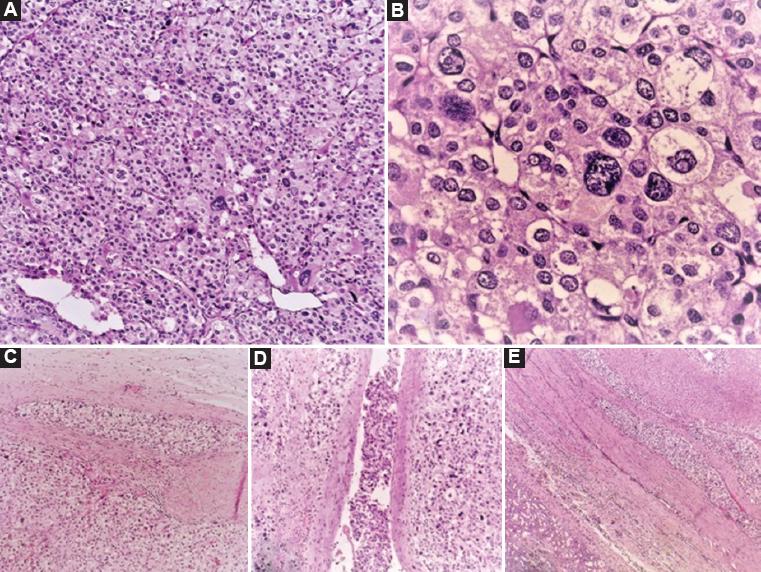

Varón de 43 años con diabetes mellitus tipo 2 en adecuado control. Inició con dolor de tipo cólico en el hipocondrio izquierdo, que se irradiaba a la región lumbar homolateral, con una puntuación en la escala visual análoga de 8/10, fiebre intermitente y pérdida de peso no intencionada de 10 kg en 3 meses. La tomografía de abdomen contrastada evidenció un tumor dependiente de la glándula suprarrenal izquierda, de 10 × 12 cm, de 91 unidades Hounsfield (UH) y realce a 167 UH tras la aplicación de medio de contraste, que desplazaba las estructuras adyacentes, así como lesiones hepáticas en los segmentos VII y VIII con realce tras la aplicación de medio de contraste (Fig. 1). Las catecolaminas y las metanefrinas plasmáticas y urinarias fueron normales. Se realizó una adrenalectomía radical en bloque (Fig. 2), sin complicaciones transoperatorias, con un sangrado cuantificado en 1300 ml, adecuada evolución posoperatoria y egreso domiciliario al cuarto día. El reporte histopatológico fue de carcinoma corticoadrenal de alto grado, de 16 cm diámetro, con necrosis extensa (70%) que invade la cápsula, con presencia de invasión linfovascular focal, márgenes quirúrgicos libres de neoplasia, sin invasión a estructuras adyacentes, y con índice mitótico de 25 (Fig. 3). En la inmunohistoquímica, inhibina, Melan-A y Ki-67 (40%) fueron positivas; sinaptofisina, cromogranina y S100, negativas (Fig. 4). El paciente se encuentra actualmente en protocolo para inicio de terapia sistémica.

Figura 3 Carcinoma corticoadrenal. A: patrón de crecimiento sólido con heterogeneidad celular. B: a mayor aumento se observan nucleomegalia, cromatina granular gruesa con distribución irregular e inclusiones intranucleares. C: invasión a la cápsula adrenal. D: invasión vascular. E: tumor y riñón subyacente sin invasión (tinción de hematoxilina y eosina).

Existen factores pronósticos que pueden predecir la sobrevida del paciente, como el índice de proliferación Ki-67 > 20% y la puntuación de Weiss (grado nuclear, índice de mitosis en campo de alta frecuencia, figuras mitóticas atípicas, células claras < 25%, arquitectura difusa > 33% del tumor, necrosis, invasión vascular, invasión sinusoidal, invasión capsular) > 6, que se han asociado a un pronóstico pobre11-13. Los predictores más importantes de supervivencia en estos pacientes son el grado tumoral, el estadio tumoral y la resección quirúrgica13.

En el diagnostico histopatológico desempeña un papel importante la inmunohistoquímica para confirmar el origen adrenocortical. Existen diferentes biomarcadores que pueden plantear el diagnóstico, por lo que es importante conocer la especificidad y la sensibilidad de cada uno. El factor esteroidogénico 1 se considera el más confiable y específico, ya que se expresa en la corteza suprarrenal no tumoral y en neoplasias corticales, considerándose distintivo de tejidos esteroidogénicos; tiene una especificidad del 100% y una sensibilidad del 98-100%14. Melan-A se ha descrito en tejido esteroidogénico, con una sensibilidad y una especificidad superiores al 95%. Exiten otros biomarcadores, como inhibina alfa, calretinina y D2-40, que se pueden expresar en tumores adrenales y de celulas mesoteliales. Ki-67, como ya se ha mencionado, tiene valor pronóstico para el diagnóstico y la sobrevida. La cromogranina A suele ser negativa en el CCA y positiva en el feocromocitoma.

En nuestro paciente, sin evidencia clínica ni bioquímica de funcionalidad, que debutó como enfermedad avanzada con un estadio clínico IV, con actividad metastásica hepática, fue necesaria la resección en bloque, obteniendo unos márgenes negativos en la pieza quirúrgica. Aun así, es necesaria terapia sistémica adyuvante. Sin embargo, el pronóstico es malo debido por su puntuación de Weiss de 7 puntos, el Ki-67 del 40% y el estadio clínico IV, por lo que la probabilidad de sobrevivir 5 años será menor del 13%.